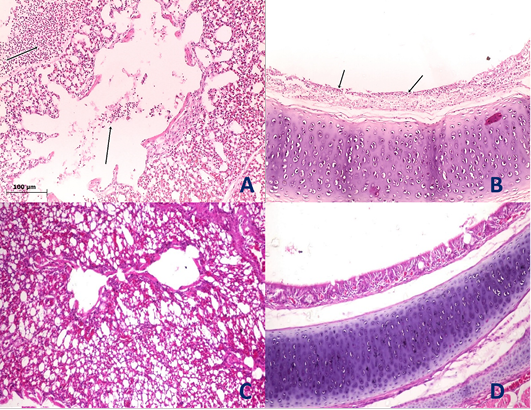

Histological section of lung and trachea of the infected and non-infected group at 5th day post infection (dpi). A, lung showed moderate pneumonia with inflammatory exudate inside tertiary bronchi and secondary bronchi (arrow) with necrosed tertiary bronchi lining; B, trachea revealed tracheitis with noticeable necrosis of lining epithelium and mononuclear cells infiltration (arrow); C, normal lung (non-infected group) with no histopathological alterations; D, normal trachea (non-infected group) with no histopathological alterations.